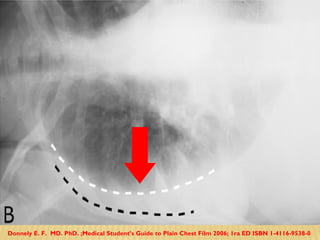

Densa opacidad en base derecha con borramiento del hemidiafragma correspondiente y la parrilla costal

Hemitorax derecho: Derrame pleural Hemitorax Izquierdo: Derrame sub pulmonar

Derrame subpulmonar: Opacificación como velo en hemitorax izquierdo Elevación del hemidiafrágma Desplazamiento de la cúpula gástrica

Donnely E. F.  MD. PhD. ;Medical Student’s Guide to Plain Chest Film 2006; 1ra ED ISBN 1-4116-9538-0